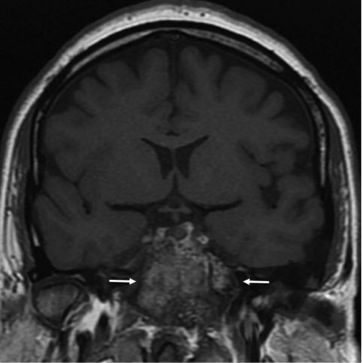

- На МРТ головного мозгавизуализирована микроаденома аденогипофиза размерами 7×6 мм (рис. 3) с инфраселлярным распространением, а также признаки диффузного утолщения левой верхнечелюстной и клиновидной пазух, клиновидной кости, латеральной стенки левой глазницы, базилярной части затылочной кости по типу фиброзной дисплазии (рис. 4).

Рис. 3. Пациентка М. МРТ головного мозга. Микроаденома гипофиза с пара-инфраселлярным распространением.

Описание. Турецкое седло деформировано, в правой части дно турецкого седла локально углублено. Структура аденогипофиза неоднородна за счет кистозно-солидного образования в его правой части, размерами 7×6 мм. Образование распространяется в пазуху основной кости.

Рис. 4. Пациентка М. МРТ. Фиброзная дисплазия клиновидной кости.

Описание. Субтотальная обтурация пазухи основой кости. В левой верхнечелюстной пазухе, преимущественно по передней стенке, в левой клиновидной пазухе и клиновидной кости (теле и левом крыле), в задних ячейках решетчатого лабиринта, базилярной части затылочной кости (больше слева), в латеральной стенке левой глазницы, в затылочной чешуе определяется диффузное утолщение костей по типу фиброзной дисплазии, с наличием в структуре кистозных включений.